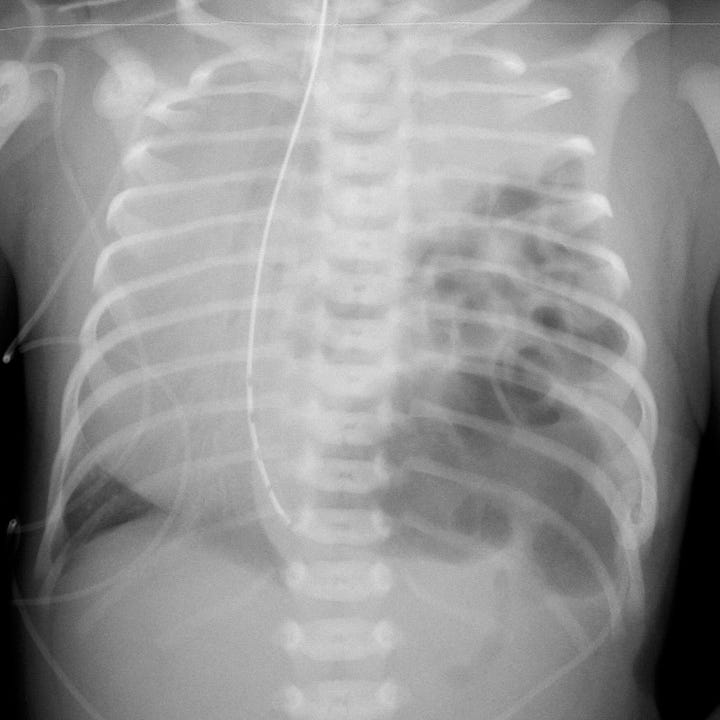

CDH is often diagnosed by prenatal ultrasound and is sometimes surgically repaired in utero. It may not be detected until after a child is born, and in that case CDH is a surgical emergency. If the defect is large enough, neonates may develop respiratory distress and cyanosis in the first hours of life. Clinical findings include decreased breath sounds and intrathoracic bowel sounds on the affected side. Plain radiographs show intrathoracic bowel or viscera with contralateral mediastinal shift and compressive atelectasis or hypoplasia of the ipsilateral lung. A gasless abdomen may be seen if most bowel loops have herniated into the hemithorax. Ultrasound confirms the clinical radiographic diagnosis and can identify any herniated solid organs.

Congenital diaphragmatic hernia in two newborns. Air-filled bowel fills the inferior aspect of the left hemithoraces, with rightward mediastinal shift and compression of airless, hypoplastic left lungs.